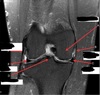

What is letter A?

MEDIAL FEMORAL CONDYLE

126

What is letter B?

MEDIAL COLLATERAL LIGAMENT

127

What is letter C?

MEDIAL MENISCUS

128

What is letter D?

TIBIAL PLATEAU

129

What is letter E?

LATERAL MENISCUS

130

What is letter F?

LATERAL COLLATERAL LIGAMENT

131

PATELLA

132

FEMUR

133

ANTERIOR HORN OF LATERAL MENISCUS

134

TIBIA

135

HEAD OF FIBULA

136

POSTERIOR HORN OF LATERAL MENISCUS

137

QUADRICEPS TENDON

138

139

PATELLA TENDON

140

141

POSTERIOR CRUCIATE LIGAMENT

142

DISTAL FEMUR